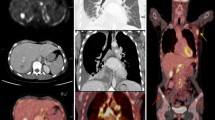

Tanjea et al. assessed the utility of [18F]FDG PET/MRI in the initial staging of breast carcinoma (Taneja et al. 2014). In this study 36 patients with breast cancer underwent dedicated breast primary and nodal as well as whole body staging (Fig. 6.3). The study showed a sensitivity of 60% and 93.3% for PET and MRI. In the detection of axillary lymph nodes metastases there was a specificity of 91% for both and a false-negative rate of 6.7% on MRI and 40% on [18F]FDG PET. [18F]FDG PET/MRI increased diagnostic confidence for nodal involvement. Distant metastases were found in 22% of patients at the time of diagnosis. Overall [18F]FDG PET/MRI led to a change in management in 12 (33.3%) patients. The authors conclude that in this pilot study simultaneous [18F]FDG PET/MRI has been useful in whole-body initial staging of breast cancer patients. Eun-Jung Kong et al. investigated the application of combined whole-body and dedicated [18F]FDG PET/MRI of the breast in 42 breast cancer patients (Kong et al. 2014). They authors conclude that such a “one-stop-shopping” examination is feasible and facilitates the benefits of combining high-resolution local breast and whole-body staging with metabolic images. They found that [18F]FDG breast PET/MRI utilizing a dedicated coil is still necessary to enable an accurate diagnosis and staging of invasive carcinomas that are less than 1 cm in size.

Invasive ductal cancer in the right breast (thick arrows). 1 min subtraction MIP image (a) [18F]FDG PET/MRI fused axial (b) show a metabolically active mass with satellite lesions. STIR axial (d) and [18F]FDG PET/MRI fused axial (e) showing [18F]FDG avid marrow lesion in the right iliac bone (thin arrows in (d) and (e)). [18F]FDG PET/MRI MIP image (g) shows multiple focal hypermetabolic areas (thick arrows). STIR sagittal (h) and [18F]FDG PET/MRI fused sagittal (i) show multiple mildly [18F]FDG avid marrow lesions in vertebrae (arrow heads). 1 min subtraction MIP image (c) STIR axial (f) and STIR sagittal (j) show marked regression of primary breast as well as osseous lesions after chemotherapy. Reprinted with permission from: Taneja S, Jena A, Goel R, Sarin R, Kaul S. Simultaneous whole-body 18F-FDG PET-MRI in primary staging of breast cancer: a pilot study. Eur J Radiol. 2014;83(12):2231–9